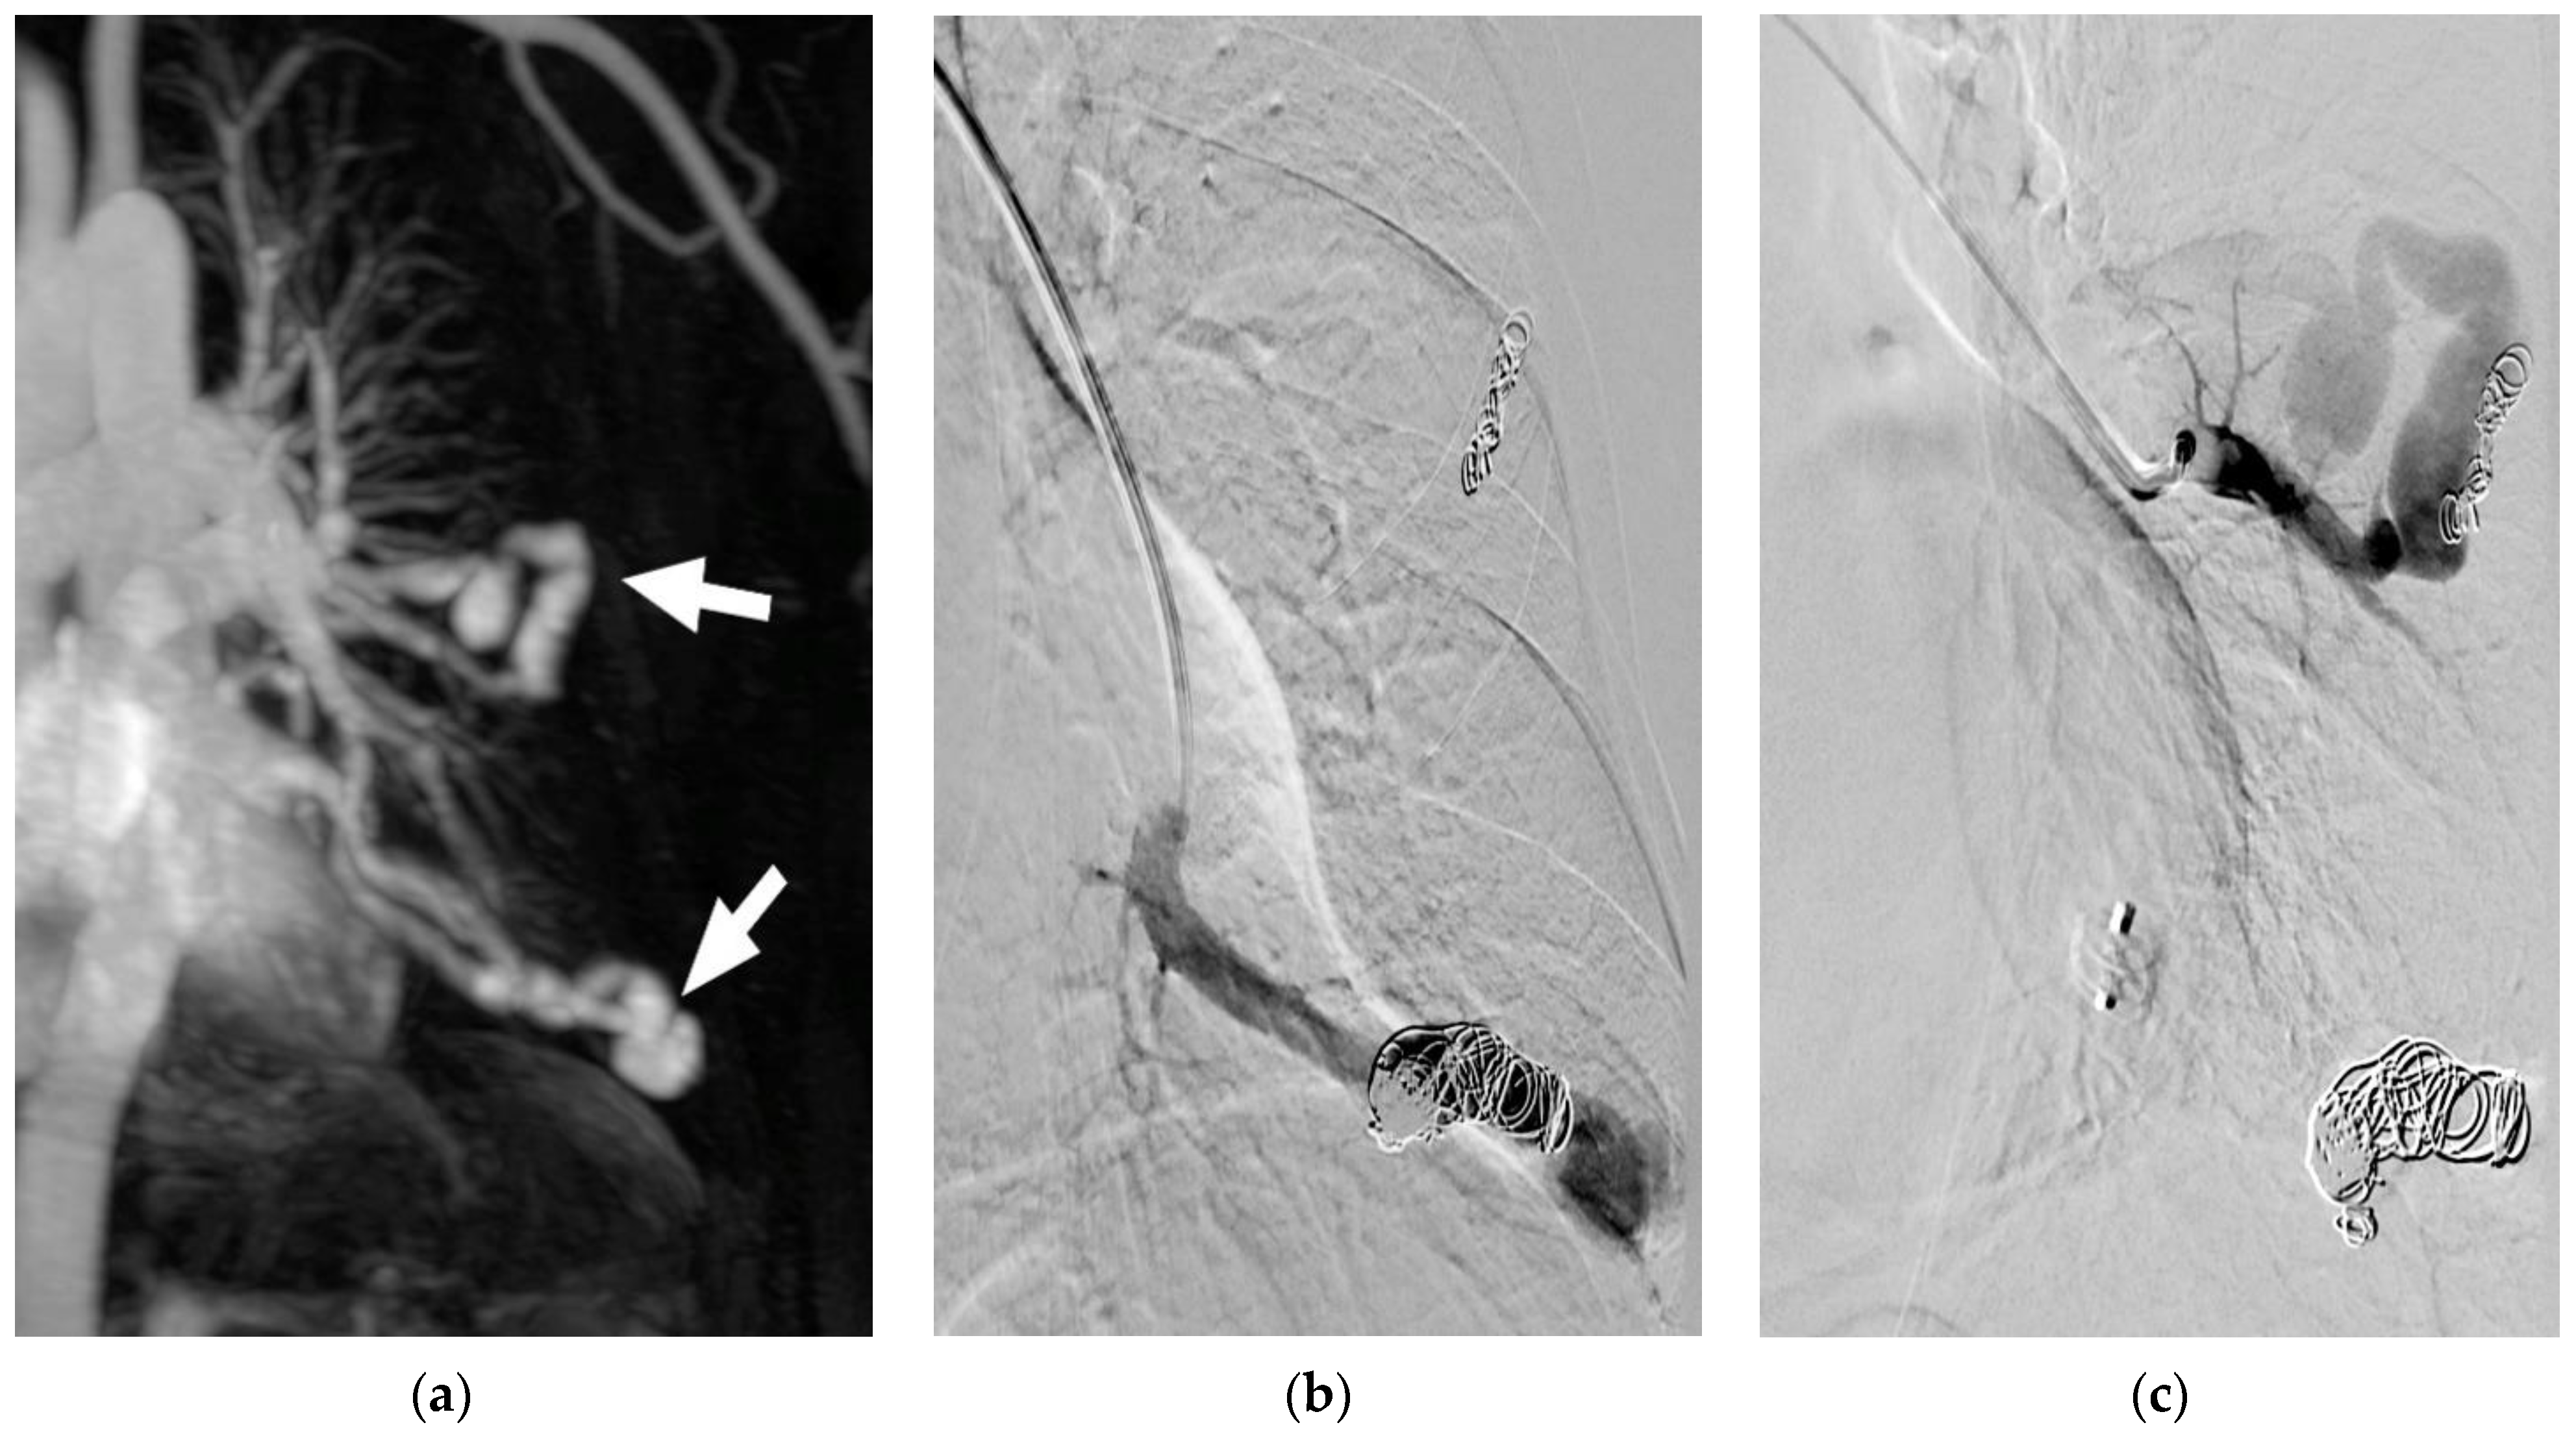

Figure 2. (ac) CT of a patient, demonstrating a giant complex PAVM of the right lung (a). The PAVM is depicted after selective catheterization of the feeding artery on DSA after manual contrast medium injection (b). DSA of the PAVM directly after positioning of an amplatzer vascular plug II (arrow) with already reduced flow in the PAVM (c).